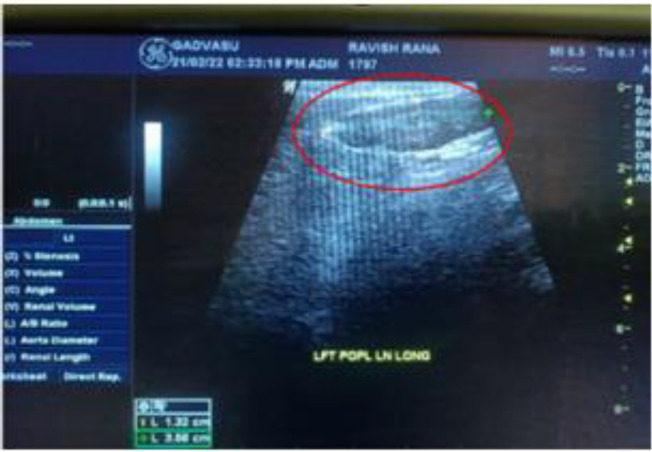

Methods: A total of 123 samples (100 lymph node aspirates, 15 lymph node tissues, and 8 blood samples) from 83 dogs suspected of lymphadenitis accompanied by gastroenteritis, chronic skin infections, immunosuppression, chronic pulmonary diseases, and other chronic undiagnosed diseases were studied. The samples were processed for cytological and microscopic examination by Ziehl-Neelsen staining. Following the decontamination procedure, the aspiration and lymph node tissue samples were inoculated into Middlebrook 7H11 media for up to 8 weeks. The aspirated material was also directly used for molecular detection by triplex-nested polymerase chain reaction (nPCR) assay.

Results: A cytological study revealed pyogranulomatous inflammation of the lymph node tissue. Impression smears from lymph node tissues displayed the presence of acid-fast organisms. Out of 83 cases of dogs, 8 were found to be positive for Mycobacterium spp. Among those 8 positive cases, 3 were confirmed to belong to MAC, and 5 belonged to the Mycobacterium tuberculosis complex (MTB complex).